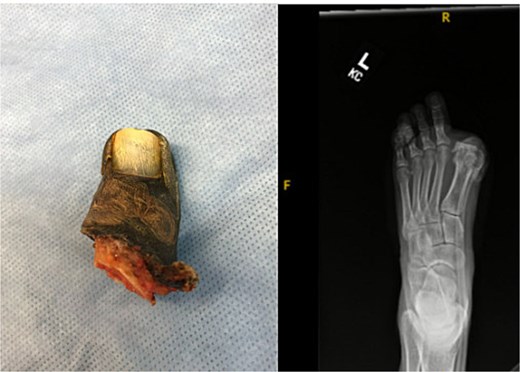

On postoperative day 1, the great toe became blue and painful. Vascular consultation was obtained. Angiography demonstrated impaired distal perfusion without a correctable lesion. Despite wound care, debridement, hyperbaric oxygen therapy, and oral cephalexin, the toe progressed to dry gangrene involving the entire hallux (Fig. 2). On examination, gangrene extended to the MTP joint with surrounding hyperemia but no erythema. The hallux lacked capillary refill and sensation, yet dorsalis pedis and posterior tibial pulses were 2+ (normal amplitude). Sensation and motor strength in the lesser toes were intact.

Gross specimen of amputated hallux (left) and postoperative radiograph following metatarsophalangeal joint amputation and screw removal.